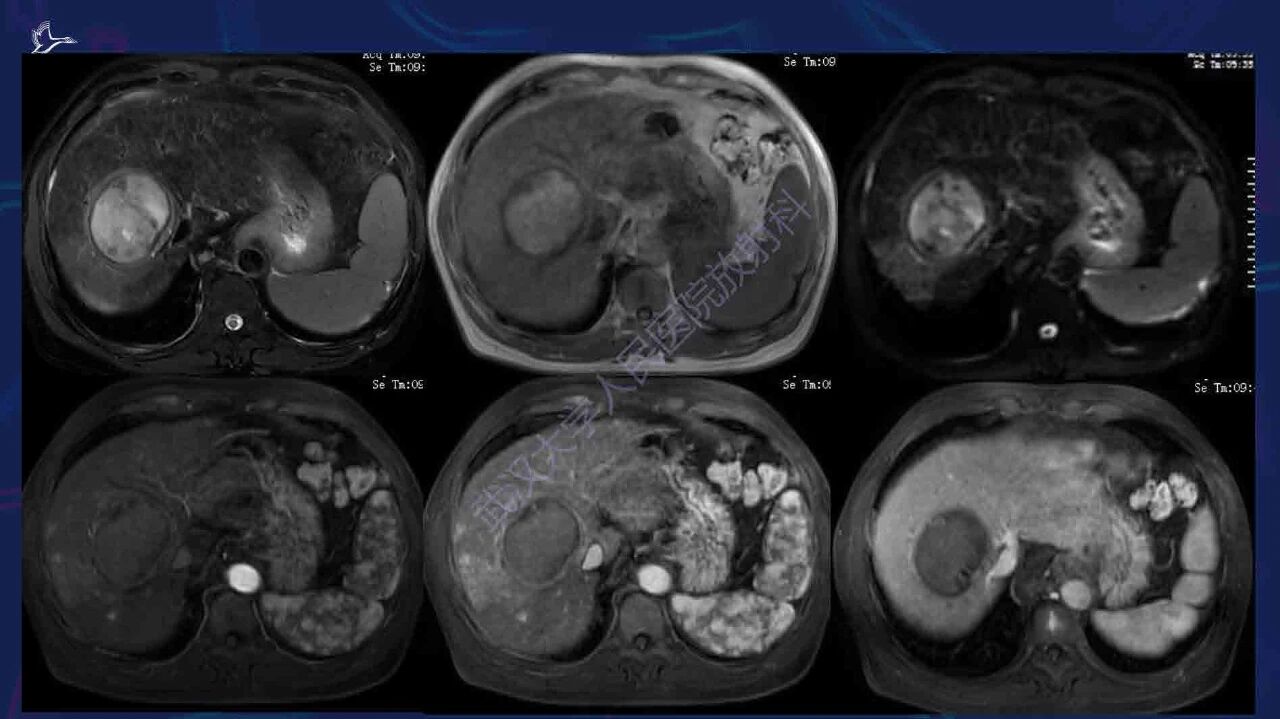

肝硬化伴肝内局灶性病变影像诊断